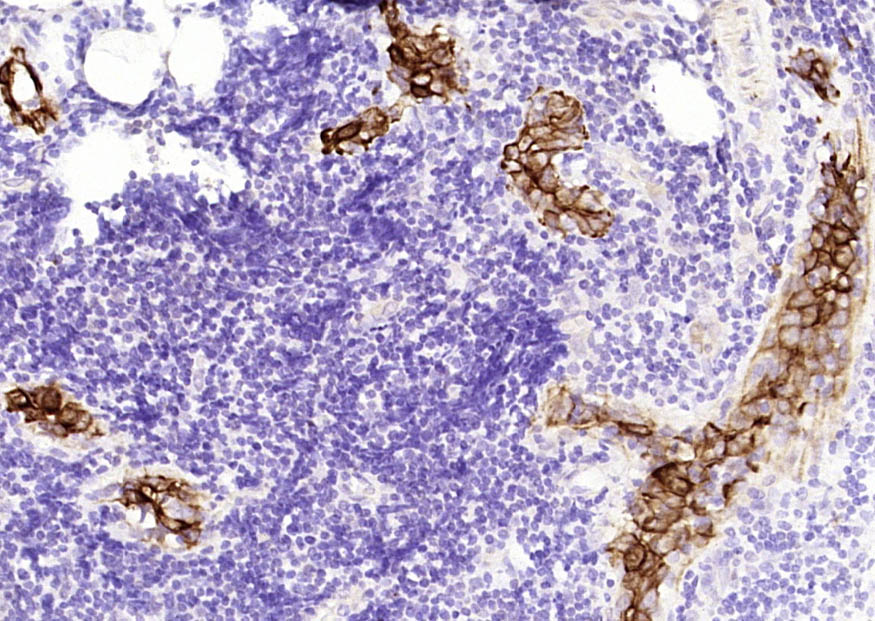

Vimentin is a developmentally regulated intermediate filament protein (IFP) found in cells of mesenchymal origin. It is believed to be involved with the intracellular transport of proteins between the nucleus and plasma membrane. Unlike other IFP proteins, vimentin is expressed, along with desmin, during the early stages of cellular development. During the development process, vimentin is exchanged for new, tissue-specific IFPs. Vimentin has been implicated to be involved in the rate of steroid synthesis via its role as a storage network for steroidogenic cholesterol containing lipid droplets. Vimentin phosphorylation by a protein kinase causes the breakdown of intermediate filaments and activation of an ATP and myosin light chain dependent contractile event. This results in cytoskeletal changes that facilitate the interaction of the lipid droplets within mitochondria, and subsequent transport of cholesterol to the organelles leading to an increase in steroid synthesis.

| IHC-P | Human, Mouse, Rat | 1:100-500 | |